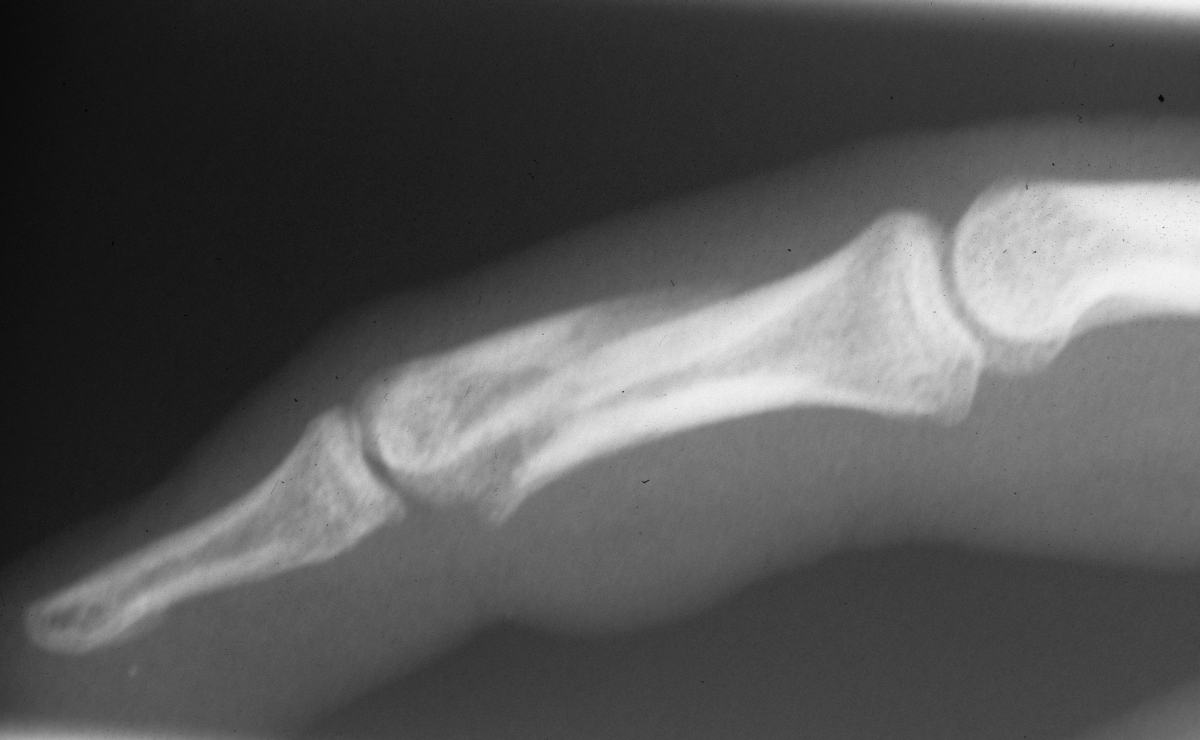

Case 3

Acute mallet fracture treated with percutaneous

pinning: proximal pin stabilizes the fracture

fragment, longitudinal pin maintains distal phalanx

position. |

| Thermoplastic bonding of the protruding ends: appearance at one month. |

| Late result. |